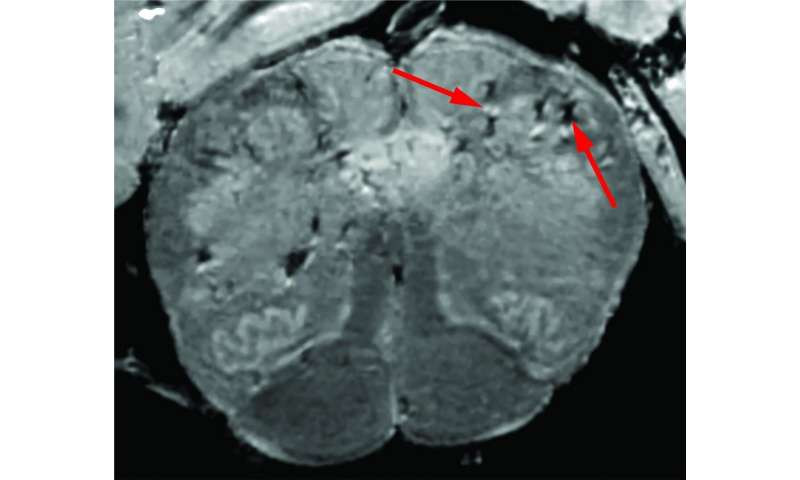

Ban đầu, các nhà nghiên cứu sử dụng máy quét hình ảnh cộng hưởng từ (MRI) đặc biệt, công suất cao, nhạy hơn từ 4 đến 10 lần so với hầu hết các máy quét MRI, để kiểm tra các mẫu khứu giác và não của từng bệnh nhân. Những vùng này được cho là rất nhạy cảm với COVID-19. Củ khứu giác kiểm soát khứu giác của chúng ta trong khi thân não kiểm soát nhịp thở và nhịp tim của chúng ta.

Kết quả quét cho thấy cả hai vùng đều có rất nhiều điểm sáng, được gọi là cường độ cao, thường chỉ ra tình trạng viêm và các điểm tối, được gọi là mất cường độ, biểu hiện chảy máu.

Sau đó, các nhà nghiên cứu sử dụng bản quét như một hướng dẫn để kiểm tra các điểm này kỹ hơn dưới kính hiển vi. Họ phát hiện ra rằng những điểm sáng chứa các mạch máu mỏng hơn bình thường và đôi khi làm rò rỉ các protein trong máu, như fibrinogen, vào não.

Điều này dường như kích hoạt phản ứng miễn dịch. Các đốm này được bao quanh bởi các tế bào T từ máu và các tế bào miễn dịch của não được gọi là microglia. Ngược lại, các đốm đen chứa cả mạch máu đông và rò rỉ nhưng không có phản ứng miễn dịch.